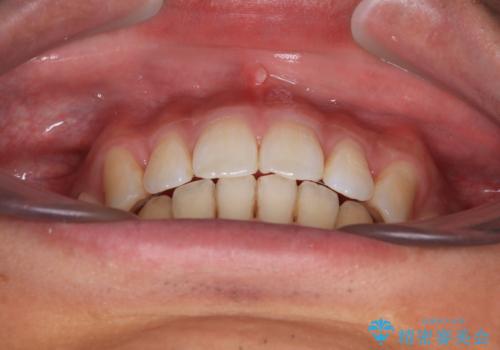

深い咬み合わせと前歯の隙間 ハーフリンガルによる矯正治療

- 咬み合わせにより上顎正中に隙間ができているとのことで来院された患者様です。

インビザラインは自己管理が煩わしく、表側のワイヤー装置は目立つので避けたいとのことで、上顎だけが裏側装置のハーフリンガルにて矯正治療を行うこととしました。